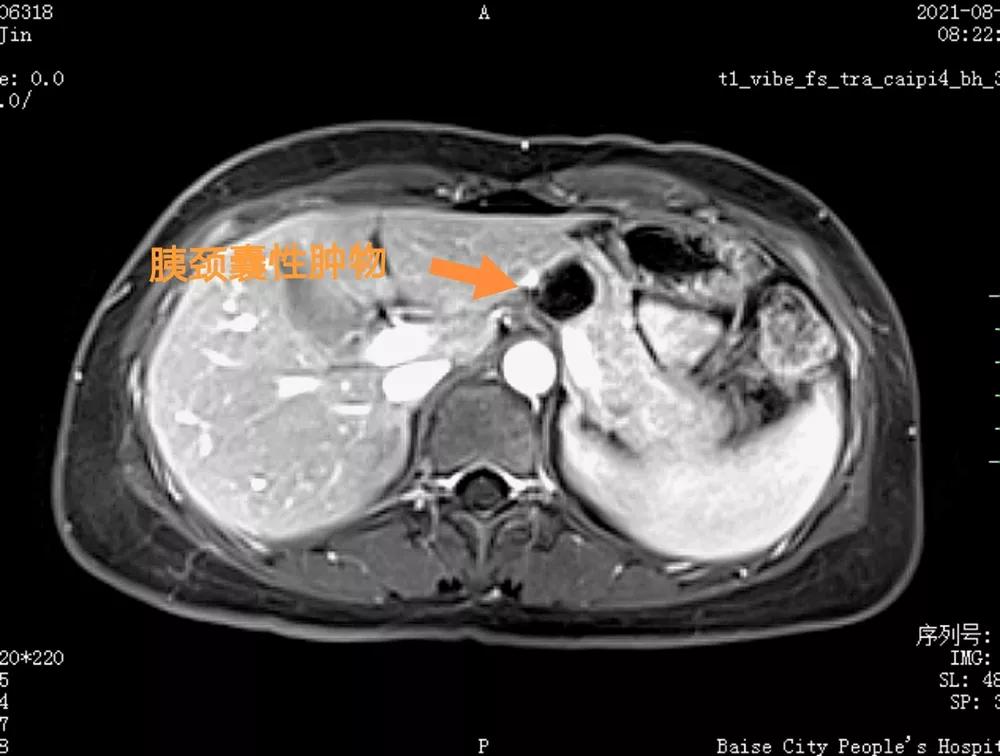

患者术前MRI检查

患者为一名34岁女性,2个多月前体检时发现胰腺有肿物。发现肿瘤后,患者曾到多家医院就诊,得到的答复均为“肿瘤紧邻脾动脉和脾静脉,手术风险较大,需采用传统开腹手术”。最后患者选择到百色市人民医院肝胆外科住院诊治。钟腾猛主任带领手术团队经仔细分析患者病情、影像学资料后,对患者情况进行研判,认为患者符合行全腔镜下胰腺中段切除术。经患者同意,肝胆外科团队随即进行了术前准备。